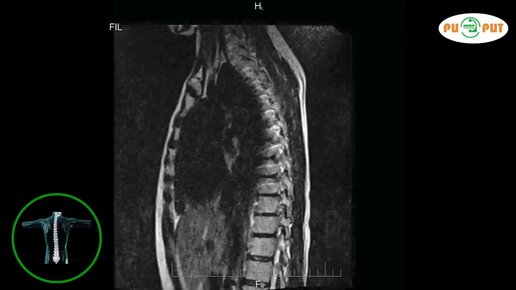

Как делают МРТ всего позвоночника (видео)